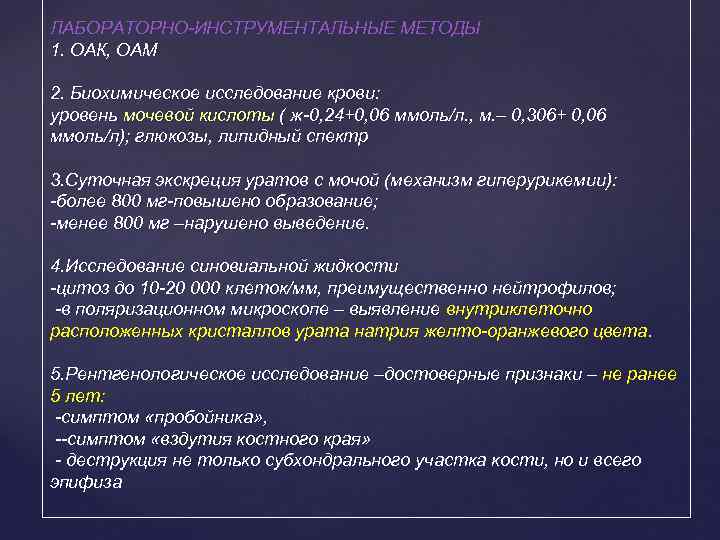

ЛАБОРАТОРНО-ИНСТРУМЕНТАЛЬНЫЕ МЕТОДЫ 1. ОАК, ОАМ 2. Биохимическое исследование крови: уровень мочевой кислоты ( ж-0, 24+0, 06 ммоль/л. , м. – 0, 306+ 0, 06 ммоль/л); глюкозы, липидный спектр 3. Суточная экскреция уратов с мочой (механизм гиперурикемии): -более 800 мг-повышено образование; -менее 800 мг –нарушено выведение. 4. Исследование синовиальной жидкости -цитоз до 10 -20 000 клеток/мм, преимущественно нейтрофилов; -в поляризационном микроскопе – выявление внутриклеточно расположенных кристаллов урата натрия желто-оранжевого цвета. 5. Рентгенологическое исследование –достоверные признаки – не ранее 5 лет: -симптом «пробойника» , --симптом «вздутия костного края» - деструкция не только субхондрального участка кости, но и всего эпифиза

ЛАБОРАТОРНО-ИНСТРУМЕНТАЛЬНЫЕ МЕТОДЫ 1. ОАК, ОАМ 2. Биохимическое исследование крови: уровень мочевой кислоты ( ж-0, 24+0, 06 ммоль/л. , м. – 0, 306+ 0, 06 ммоль/л); глюкозы, липидный спектр 3. Суточная экскреция уратов с мочой (механизм гиперурикемии): -более 800 мг-повышено образование; -менее 800 мг –нарушено выведение. 4. Исследование синовиальной жидкости -цитоз до 10 -20 000 клеток/мм, преимущественно нейтрофилов; -в поляризационном микроскопе – выявление внутриклеточно расположенных кристаллов урата натрия желто-оранжевого цвета. 5. Рентгенологическое исследование –достоверные признаки – не ранее 5 лет: -симптом «пробойника» , --симптом «вздутия костного края» - деструкция не только субхондрального участка кости, но и всего эпифиза